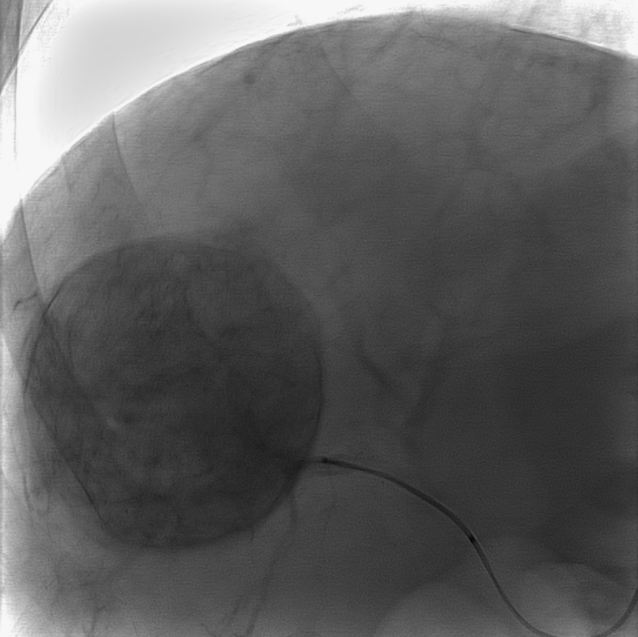

Pancreatic

#AVM with multiple arterial feeders and single outflow into splenic vein branch. Treated via#transportal approach with#coils and a plug. No more AVM. Fun way to start 2020.@MountSinaiIR@GESTSymposium@SIRspecialists@SIRRFS@ISETNewspic.twitter.com/1KRDZIJlPSHvala. Twitter će to iskoristiti za poboljšanje vaše vremenske crte. PoništiPoništi -